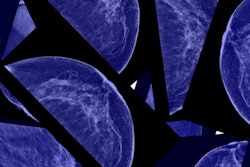

Medical technology company Nanox has inked a deal with computer-aided detection software developer CureMetrix to integrate the firm's breast imaging artificial intelligence (AI) software into its upcoming Nanox Cloud software platform.

Nanox Cloud is designed to support an end-to-end medical imaging service, offering an image repository, radiologist matching, online and offline diagnostic review and annotation, billing, reporting, and connectivity to AI software, according to the vendor.